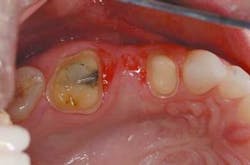

Tooth No. 14 had been previously restored with a five-surface amalgam. The buccal cusps were undermined with supragingival cracks. Further, there was recurrent caries, starting at the gingival margin on the distal. Tooth No. 12 was a virgin premolar, and it was decided to sacrifice the integrity of this tooth for what appeared to be a predictable abutment for a three-unit bridge.

On the preparation day, the patient was anesthetized with one carpule of 2 percent Septocaine. Both bridge abutments were prepared the same way with 1.5 mm occlusal reduction prepared with a KS 2 coarse 1.4 mm round-tipped, straight diamond bur (Brasseler) and a coarse diamond football (Brasseler). The facial and lingual surfaces were prepared with a KS 2 coarse, followed by a KS 1 fine for smoothing and final contouring. The inter-proximal contacts were prepared with a KS 0 coarse 1.0 mm round-tipped, straight diamond bur (Brasseler). Although crack propagation may not be a concern with the Lava All-Ceramic System, which was utilized to develop the bridge, still prepare the teeth to be very smooth with no sharp angles to potentially propagate any cracks. The depth of reduction in the photos may seem minimal based on the shape of the original teeth. However, because the plan in the wax-up was to fill out the buccal corridor, the depth cuts were based on a thickness determined by the final wax contour, not the original tooth contour.